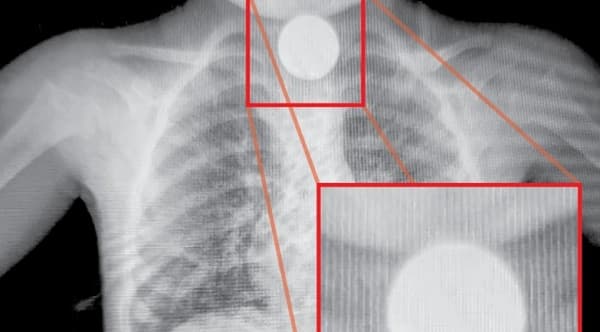

El doctor Schrodel describió las heridas como “muy graves”, especialmente en los miembros inferiores, destacando que las mordeduras fueron desgarrantes y pusieron en riesgo importantes estructuras como el tejido celular subcutáneo y los ligamentos. La gravedad de las lesiones hizo necesaria la realización de una cirugía urgente, que se estima durará entre dos y tres horas. Unite a nuestro canal de Whatsapp Además de las medidas inmediatas tomadas para atender a Ferreira, se le realizaron varios estudios y placas de radiografía para prepararla adecuadamente para el quirófano, donde los médicos esperan poder dar un diagnóstico más preciso post-operatorio. Este no es el primer incidente de este tipo para Ferreira, quien, según relatos familiares mencionados por el médico, ya había sido atacada anteriormente por sus propios animales. Fuente: Última Hora.